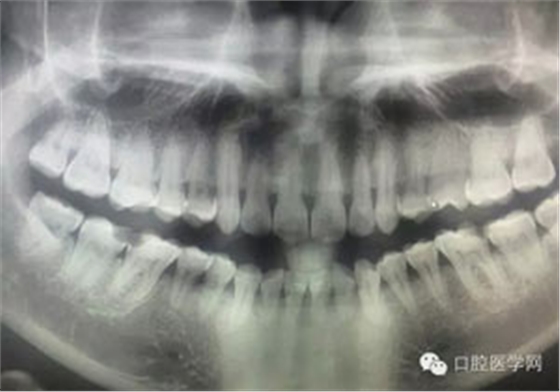

病例1:患者迫切希望保留自己的這一顆牙齒,根尖周陰影比較大,二度松動(dòng).而且旁邊有種植修復(fù)體,和患者溝通好后,治療好后觀察一個(gè)月后冠修復(fù),因?yàn)橛蟹N植的后期修復(fù),所以有了機(jī)會(huì)觀察,術(shù)后三個(gè)月和術(shù)后四個(gè)月,根尖恢復(fù)的還算不錯(cuò),希望能夠繼續(xù)觀察下去.這樣子的病例,做的時(shí)候我們一定要非常的小心,和患者要有充分的溝通以及不同科室的溝通然后決定怎么樣做比較好,假如就是出現(xiàn)了問(wèn)題,到時(shí)候我們也比較好處理些,免得我們自己到時(shí)候不好收?qǐng)觥?/span> 病例2:364647中齲的樹(shù)脂充填,現(xiàn)在樹(shù)脂的充填材料非常之多,有些時(shí)候,我們感覺(jué)有了好的材料我們就可以做出好的修復(fù),可是這是在我們有扎實(shí)的基本功的基礎(chǔ)上的,我們可以沒(méi)有那么好的樹(shù)脂,那么多的顏色選擇,修復(fù)的那么的逼真,但是我們至少要恢復(fù)患者牙齒的功能,將腐質(zhì)去除干凈,薄壁弱尖消除掉,選擇好適應(yīng)癥,給患者以盡可能好的修復(fù)。 來(lái)源于KQ88